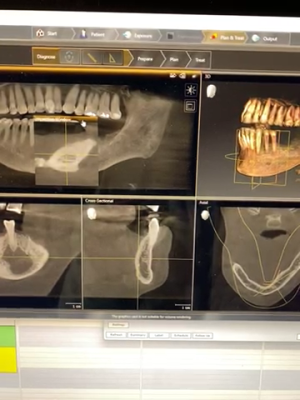

Here are his scans. Not sure if this bite is entirely accurate but there is no contact on the two centrals.

-